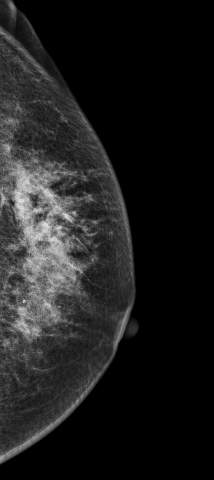

病例6 病史:患者,69岁,常规体检 2D图像:

影像描述: 在2D常规图像上并没有发现明显异常,只是感觉左乳外上象限局部不对称腺体结构有些乱,可见散在颗粒样钙化,在V-Preview(合成2D)也没有发现明显异常改变,但在3D-plane图像上我们可以明确左乳外上象限局部腺体结构紊乱,内见多颗钙化(由于医院才刚刚开展这项新技术检查医生在诊断阅片上经验不足及固有的2D阅片模式忽略了动态连续观察病灶,最后诊断为良性病变),3D动态连续薄层放大观察钙化灶我们会发现病变区钙化灶呈多形性,串珠样排列,并不是2D 和V-Preview显示的颗粒样良性钙化表现 影像诊断: 左乳外上不对称致密,考虑良性病变,BI-RADS 2级 病例点评: 病理证实:左乳导管原位癌。由此可见DBT在观察细小钙化的形态上分布上优于常规2D和V-Preview(合成2D)图像。